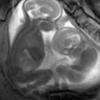

자궁안에서 ‘격투’ 벌이는 쌍둥이 생생포착

2012-12-01 나우뉴스 -